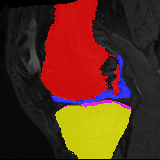

Moving Target Mono-0 Mono-5 DA-1 DA-5 Mono-200 Refer to caption Refer to caption Refer to caption Refer to caption Refer to caption Refer to caption Refer to caption Refer to caption Refer to caption Refer to caption Refer to caption Refer to caption Refer to caption Refer to caption

Figure 2:  Examples of knee MRI registration (top) and brain MRI segmentation (bottom) results. Top: The first two columns are the moving image/segmentation and the target image/segmentation followed by the warped moving images (with deformation grids)/segmentations by different models. Bottom left to right: original image, manual segmentation, and predictions of various models. Mono-i𝑖i and DA-i𝑖i represent the mono- and DA models with i𝑖i manual segmentations respectively.

Results: All trained networks are evaluated using Dice overlap scores between predictions and the manual segmentations for the segmentation network, or between the warped moving segmentations and the target segmentations for the registration network. Tabs. 1 and 2 show results for the knee and brain MRI experiments respectively in Dice scores (%). Fig. 2 shows examples of knee MRI registrations and brain MRI segmentations.

Knee results: On knee MRIs, our method improves segmentation scores over separately learned networks by about 1.2 and 0.5, and registration scores increase by about 3.1 and 3.0, when training with 5 and 10 manual segmentation respectively. Especially for the challenging cartilage structures, our joint learning boosts segmentation by 1.4 and 0.7, and registration by 5.5 and 5.2 for N=5 and N=10 respectively.

Qualitative results: DA achieves more anatomically consistent registrations than the mono-networks on the knee (Fig. 2) and Brain MRI samples (see supplementary material).

Figure 4: Examples of brain MRI registration (top) and knee MRI segmentation (bottom) results. Top: The first two columns are the moving image/segmentation and the target image/segmentation followed by the warped moving images/segmentations by different models. Bottom left to right: original image, manual segmentation, and predictions of various models. Mono-i𝑖i and DA-i𝑖i represent the mono- and DA models trained with i𝑖i manual segmentations respectively.